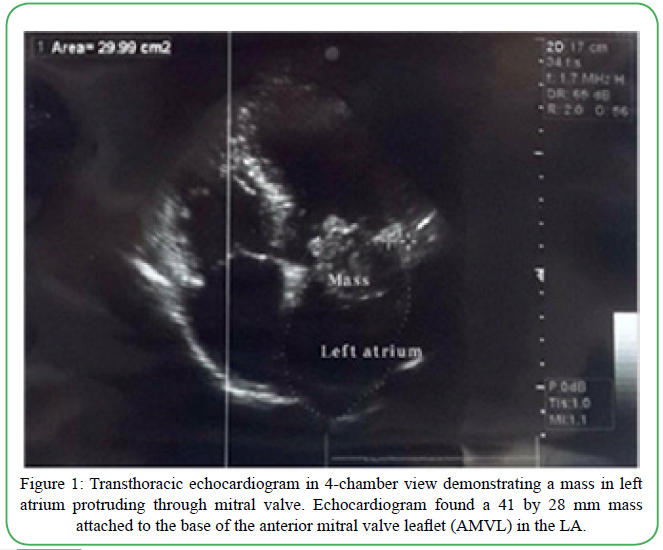

A 35-year-old Iranian otherwise healthy man was referred to the hospital with a one month history of palpitation, dyspnea on exertion, and chest discomfort. His vital signs and physical exam were unremarkable. Echocardiogram showed a heterogenous round shape mobile mass measuring 41mm x 28 mm, in the LA originating from the anterior mitral valve and protruding through the mitral valve in diastole (suggestive of either atrial myxoma or papillary fibroelastoma) (Figure 1). Computed Topography Angiography (CTA) of coronary arteries (CA) showed CA-score of 0 and a filling defect in the LA with a 35 mm protrusion to the mitral valve and attachment to the lateral left atrial wall, which also suggested atrial myxoma. A diagnosis of left atrial mass with mild mitral regurgitation and mild tricuspid insufficiency was made. Flow velocity measurements (FVM) showed that the atrial mass was producing obstruction to the flow at the mitral level (Peak Gradient = 22.11 mmHg) (Figure 2). Due to the outflow obstructive nature of the tumor, urgent cardiac surgical intervention was indicated.

Figure 1. Transthoracic echocardiogram in 4-chamber view demonstrating a mass in left atrium protruding through mitral valve. Echocardiogram found a 41 by 28 mm mass attached to the base of the anterior mitral valve leaflet (AMVL) in the LA.